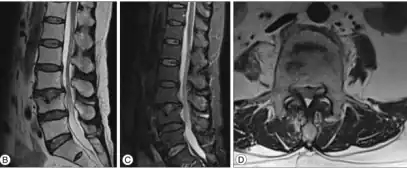

Schmorl's nodes can be detected with X-rays, although they can be imaged better by CT or MRI. They are considered to be vertical disc herniations through the cartilaginous vertebral body endplates. Schmorl's nodes can sometimes be seen radiographically, however they are more often seen on MRI, even when not visible on plain X-rays. They may or may not be symptomatic, and their etiological significance for back pain is controversial. In a study in Spine by Hamanishi, et al., Schmorl's nodes were observed on MRI in 19% of 400 patients with back pain, and in only 9% of an asymptomatic control group. The authors concluded that Schmorl's nodes are areas of "vertical disc herniation" through areas of weakness in the endplate.[4]